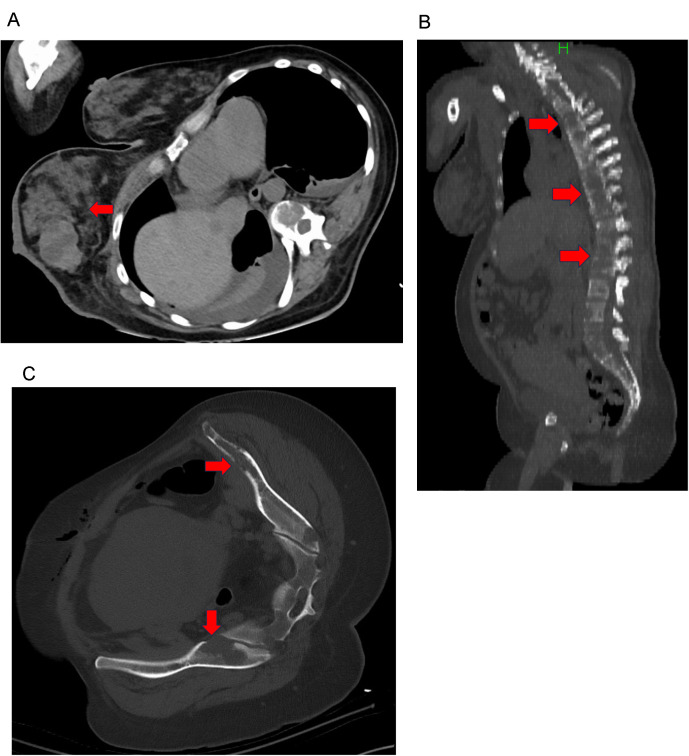

Case: A 41-year-old pregnant woman was admitted to our hospital because low back pain compromised her ability to stand. She was diagnosed with breast cancer-associated multiple bone metastases. Our unit was consulted for rehabilitation therapy, for which we formed a BMCB. The treatment was integrated and performed according to the recommendations of the BMCB. The patient underwent a cesarean section to initiate primary tumor treatment. After evaluating the risk of SREs, we provided her with rehabilitation therapy. Wearing a plastic molded thoracolumbosacral orthosis, she was able to walk with a pick-up walker. The patient continued outpatient chemotherapy and cared for her infant without experiencing any significant adverse events.

Abstract Image